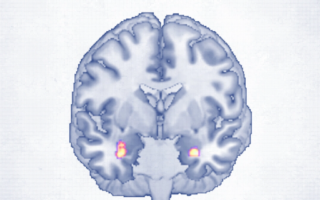

身心全方位康復:「靈魂」如何影響大腦與健康

現代健康不只關乎身體,研究指出精神參與度下降與死亡率上升有關。透過ACES健康模型,從解剖、化學、能量與靈魂四大面向全面...

感恩練習改變大腦?每晚3分鐘降焦慮穩情緒

感恩練習是否能改善焦慮與情緒穩定?研究顯示其可能影響大腦運作與壓力反應,包括情緒區域活化與荷爾蒙變化。透過簡單的睡前感恩...